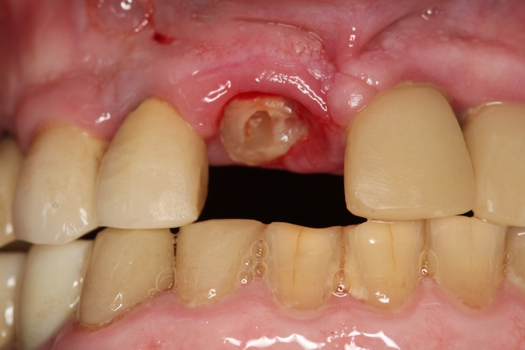

Fig 14. Immobilization splint placed 3 days after trauma.

Figure 14

A 23-year-old man reported to the dental practice on January 3. Apparently, while on vacation and celebrating the New Year, the patient experienced a loss of equilibrium and found himself horizontal in the crosswalk. When surveying the damages, his friends noticed he was missing tooth No. 8. Those who were involved were not able to find the missing maxillary central incisor. The young man was eventually seen about 3 days after the trauma. A CBCT radiograph, study models, and photographs were collected, and teeth Nos. 6 through 10 were immobilized with composite and 20 x 20 orthodontic wire (Figure 14). The CBCT and photos were emailed to the dental laboratory, and the analog intraoral impression with a centric occlusion bite registration was sent via ground transportation. Due to the nature of the trauma, the laboratory and the author expeditiously converted the analog diagnostics and merged all the patient's data sets to develop the plan. Based on the 3D data sets, the laboratory and the dentist were able to accurately assess the volume of bone and soft tissue remaining after the trauma. The volume was still intact and soft tissue was plentiful (Figure 15 and Figure 16).

The provisional abutment and treatment crown were fabricated in the laboratory with the digital proposals. Platelet-rich fibrin (PRF) clot technology was incorporated to help with soft- and hard-tissue healing (Figure 19 through Figure 21). The screw-retained provisional and the PRF clot were seated immediately after implant placement (Figure 22 and Figure 23). One 4-0 polytetrafluoroethylene suture was placed to maintain papilla. The teeth immobilization splint was placed for 6 weeks (Figure 24). The rationale for splinting teeth Nos. 6 through 10 was due to noticeable plus-2 mobility of the remaining anterior teeth. The provisional implant crown also was included in the splint.